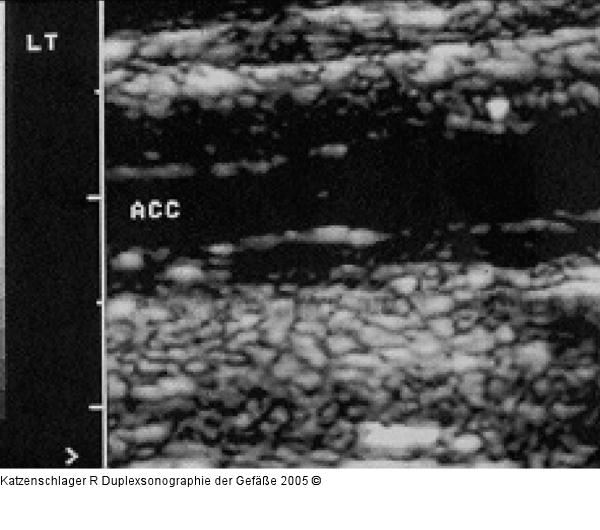

Abbildung 16: Duplexsonographie - Intima-Media

Intima-Media-Verdickung bei St. p. Radiatio |